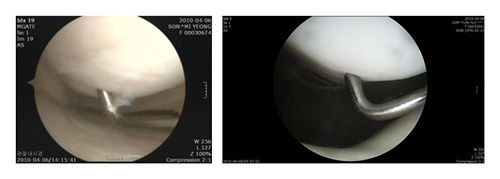

/강진수 객원기자 osenlife@osen.co.kr <사진> 연골연화증에 걸린 연골 모습(왼쪽)과 정상인 연골 모습.